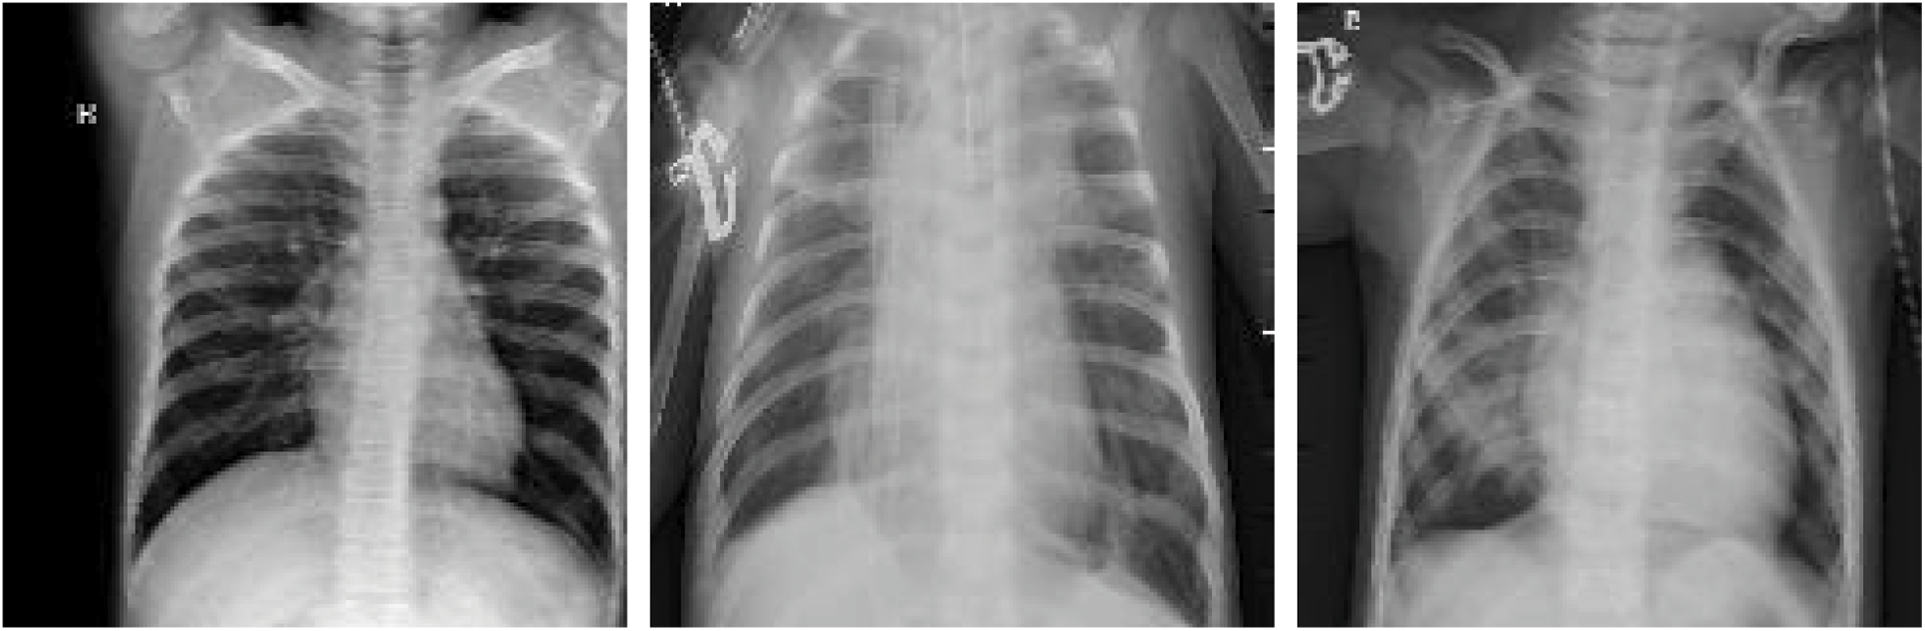

This dataset comprised chest X-ray images of lungs obtained from [29,30]. These images were selected from patients from Guangzhou Medical Center. The dataset is from an open dataset on the Internet. Generally, to obtain hospital images, they must be reviewed and approved by the patient before use. The image is in a standard image format (jpeg) and can be converted to a tensor format for use. The images were categorized into “normal” and “pneumonia” images (Fig. 10).

Figure 10: X-ray image of (a) normal person, (b) pneumonia person

The data set had 1,341 and 3,872 normal and pneumonia images, respectively (at a ratio of 1:3). If the model is trained on imbalanced data, the model is unreliable. This is because the model tends to output guesses for the imbalanced category (with more data points) during training, thus performing poorly on a real-world data set. In addition to this data imbalance problem, the total amount of images was 5,213. The model may tend to learn the category with the higher frequency rather than how to discriminate between categories when making judgments.